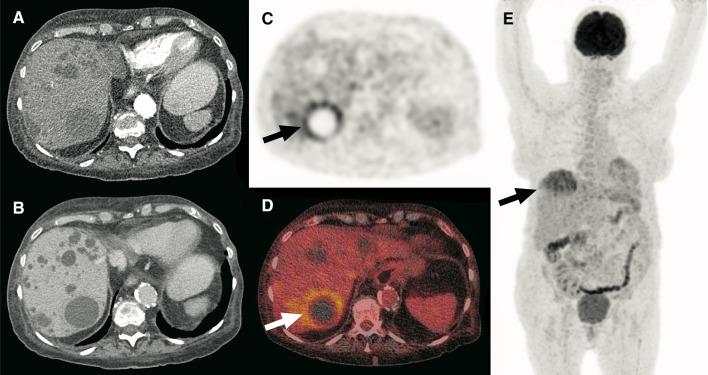

Cyst infections are a common complication in autosomal dominant polycystic kidney disease (ADPKD). Diagnosing these infections often remains challenging. Conventional imaging techniques such as ultrasonography, computed tomography (CT), and standard magnetic resonance imaging have several drawbacks and disadvantages. The purpose of this pictorial essay was to illustrate and discuss the potential value of F-fluoro-2-deoxy-d-glucose positron emission tomography (FDG-PET)/CT in diagnosing cyst infection in ADPKD.

FDG-PET/CT appears to be a sensitive method for the detection of cyst infection, but it is not infallible. Furthermore, FDG uptake in cysts and cyst-like lesions is not specific and clinical and radiological correlations are essential to improve specificity and minimize the risk of falsely discarding other diseases, in particular malignancy.

FDG-PET/CT seems to be a useful imaging modality to diagnose cyst infections in ADPKD. However, its exact diagnostic value has not been established yet due to the lack of a reliable reference standard in previous studies on this topic.